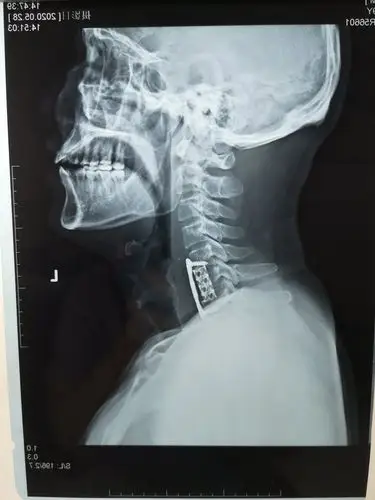

多节段退变性颈椎病的颈前路钢板固定手术治疗 - 美篇